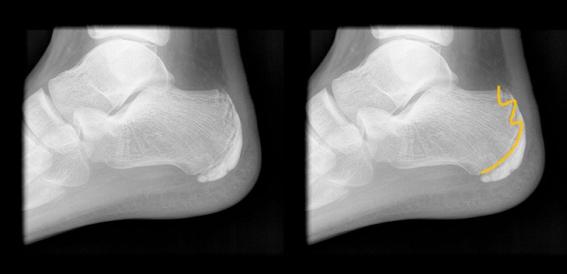

세버씨병은 방사선 촬영으로 질환의 여부를 확인할 수 있다. 방사선 촬영을 해보면 발에서 울퉁불퉁한 성장판이 관찰되기도 한다. 아킬레스 힘줄에 의해 당김이 발생할 때 더욱 불편함을 느낄 수 있다. 대부분 아이가 성장하면서 골단판이 유합돼 증상은 서서히 사라진다. 운동을 심하게 할 경우 생길 수 있는 질환인 만큼 충분한 휴식이 필수이며 증상이 심하면 염증을 가라앉히는 소염제를 먹기도 한다. 그러나 일부 증상이 악화돼 피로 골절이 동반되거나 아킬레스 힘줄 단축으로 증상이 심해지는 경우에는 족부 전문가의 진단과 치료를 받는 것이 좋다. 아이의 발에 맞는 깔창을 신발에 깔면 통증이 경감되기도 한다.